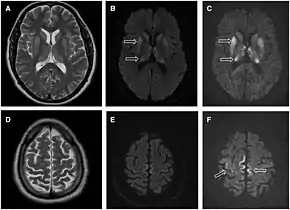

Imaging of the brain may be performed during medical evaluation, both to rule out other causes and to obtain supportive evidence for diagnosis. Imaging findings are variable in their appearance, and also variable in sensitivity and specificity.[41] While imaging plays a lesser role in diagnosis of CJD,[42] characteristic findings on brain MRI in some cases may precede onset of clinical manifestations.[43]

Brain MRI is the most useful imaging modality for changes related to CJD. Of the MRI sequences, diffuse-weighted imaging sequences are most sensitive. Characteristic findings are as follows:

- Focal or diffuse diffusion-restriction involving the cerebral cortex and/or basal ganglia. In about 24% of cases DWI shows only cortical hyperintensity; in 68%, cortical and subcortical abnormalities; and in 5%, only subcortical anomalies.[44] The most iconic and striking cortical abnormality has been called "cortical ribboning" or "cortical ribbon sign" due to hyperintensities resembling ribbons appearing in the cortex on MRI.[45] The involvement of the thalamus can be found in sCJD, is even stronger and constant in vCJD.[46]

- Varying degree of symmetric T2 hyperintense signal changes in the basal ganglia (i.e., caudate and putamen), and to a lesser extent globus pallidus and occipital cortex.[42]